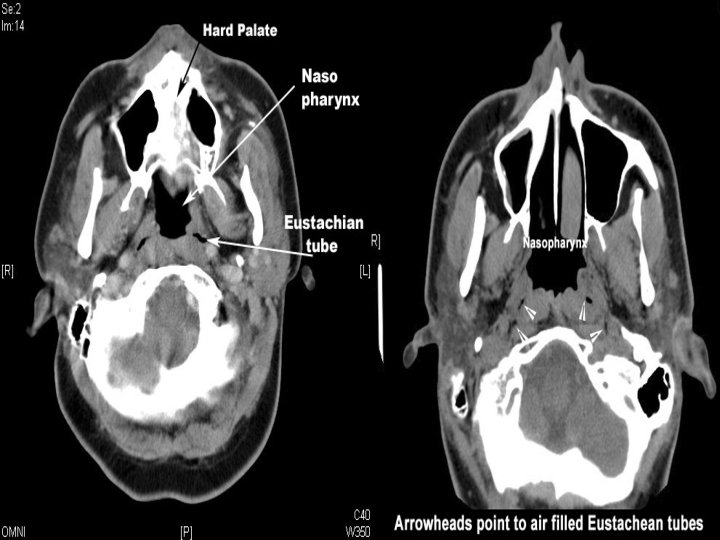

Nasopharynx Behind the nose and above the soft palate. In front it communicates through choanae with the nasal cavities The lateral wall contains the pharyngeal ostium of the ET. The pharyngeal recess (fossa of Rosenmüller) Posterosuperior wall (Basisphenoid) Pharyngobasilar fascia (Ant. To Atlas)